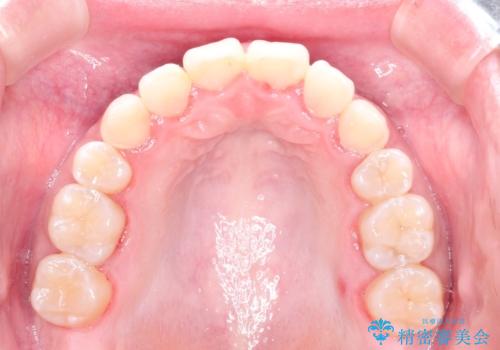

ハーフリンガル矯正 抜歯をして前歯を下げる

- 上顎の両側第1小臼歯抜歯による抜歯矯正を計画した。

上顎の抜歯により上の前歯の位置を大幅に後ろに下げることができます。

奥歯の位置関係など、様々な要素を加味し、適応を判断する必要があります。